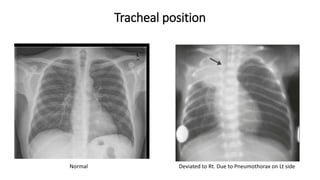

Tracheal position

Normal Deviated to Rt. Due to Pneumothorax on Lt side